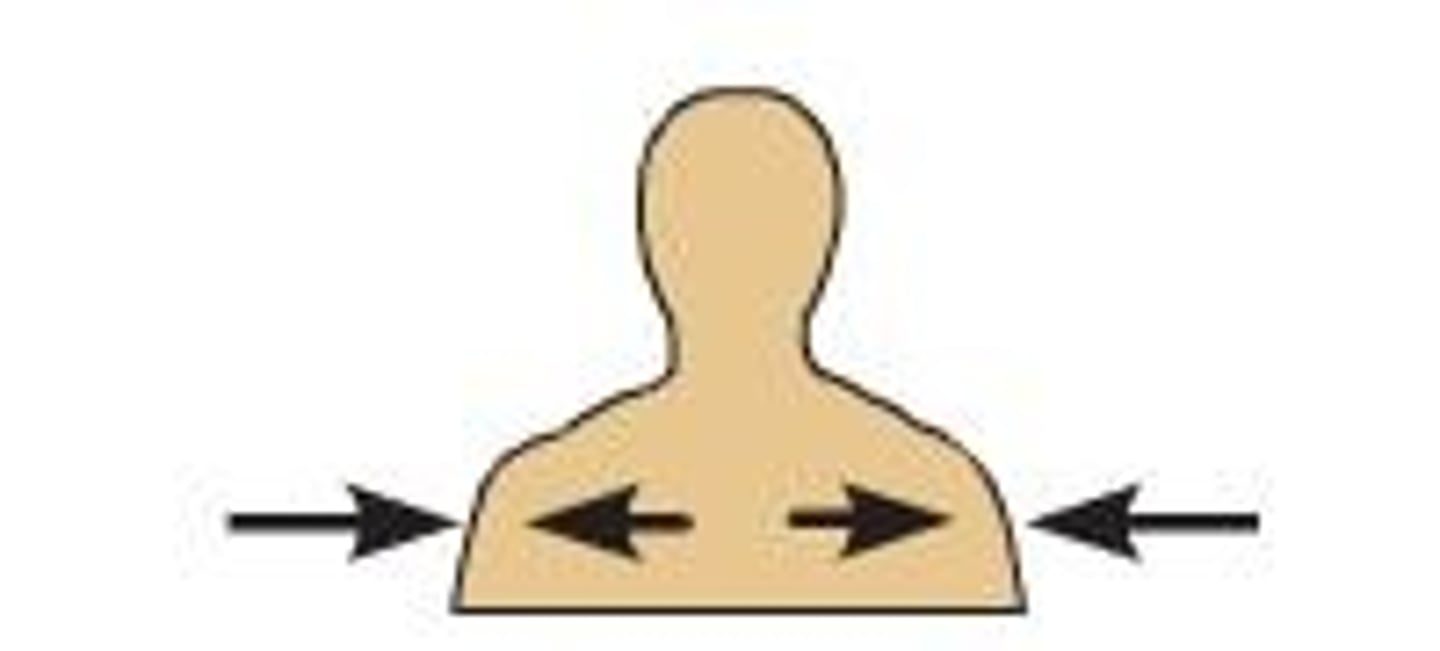

Medial

Toward the midline of the body

Lateral

Away from the midline of the body